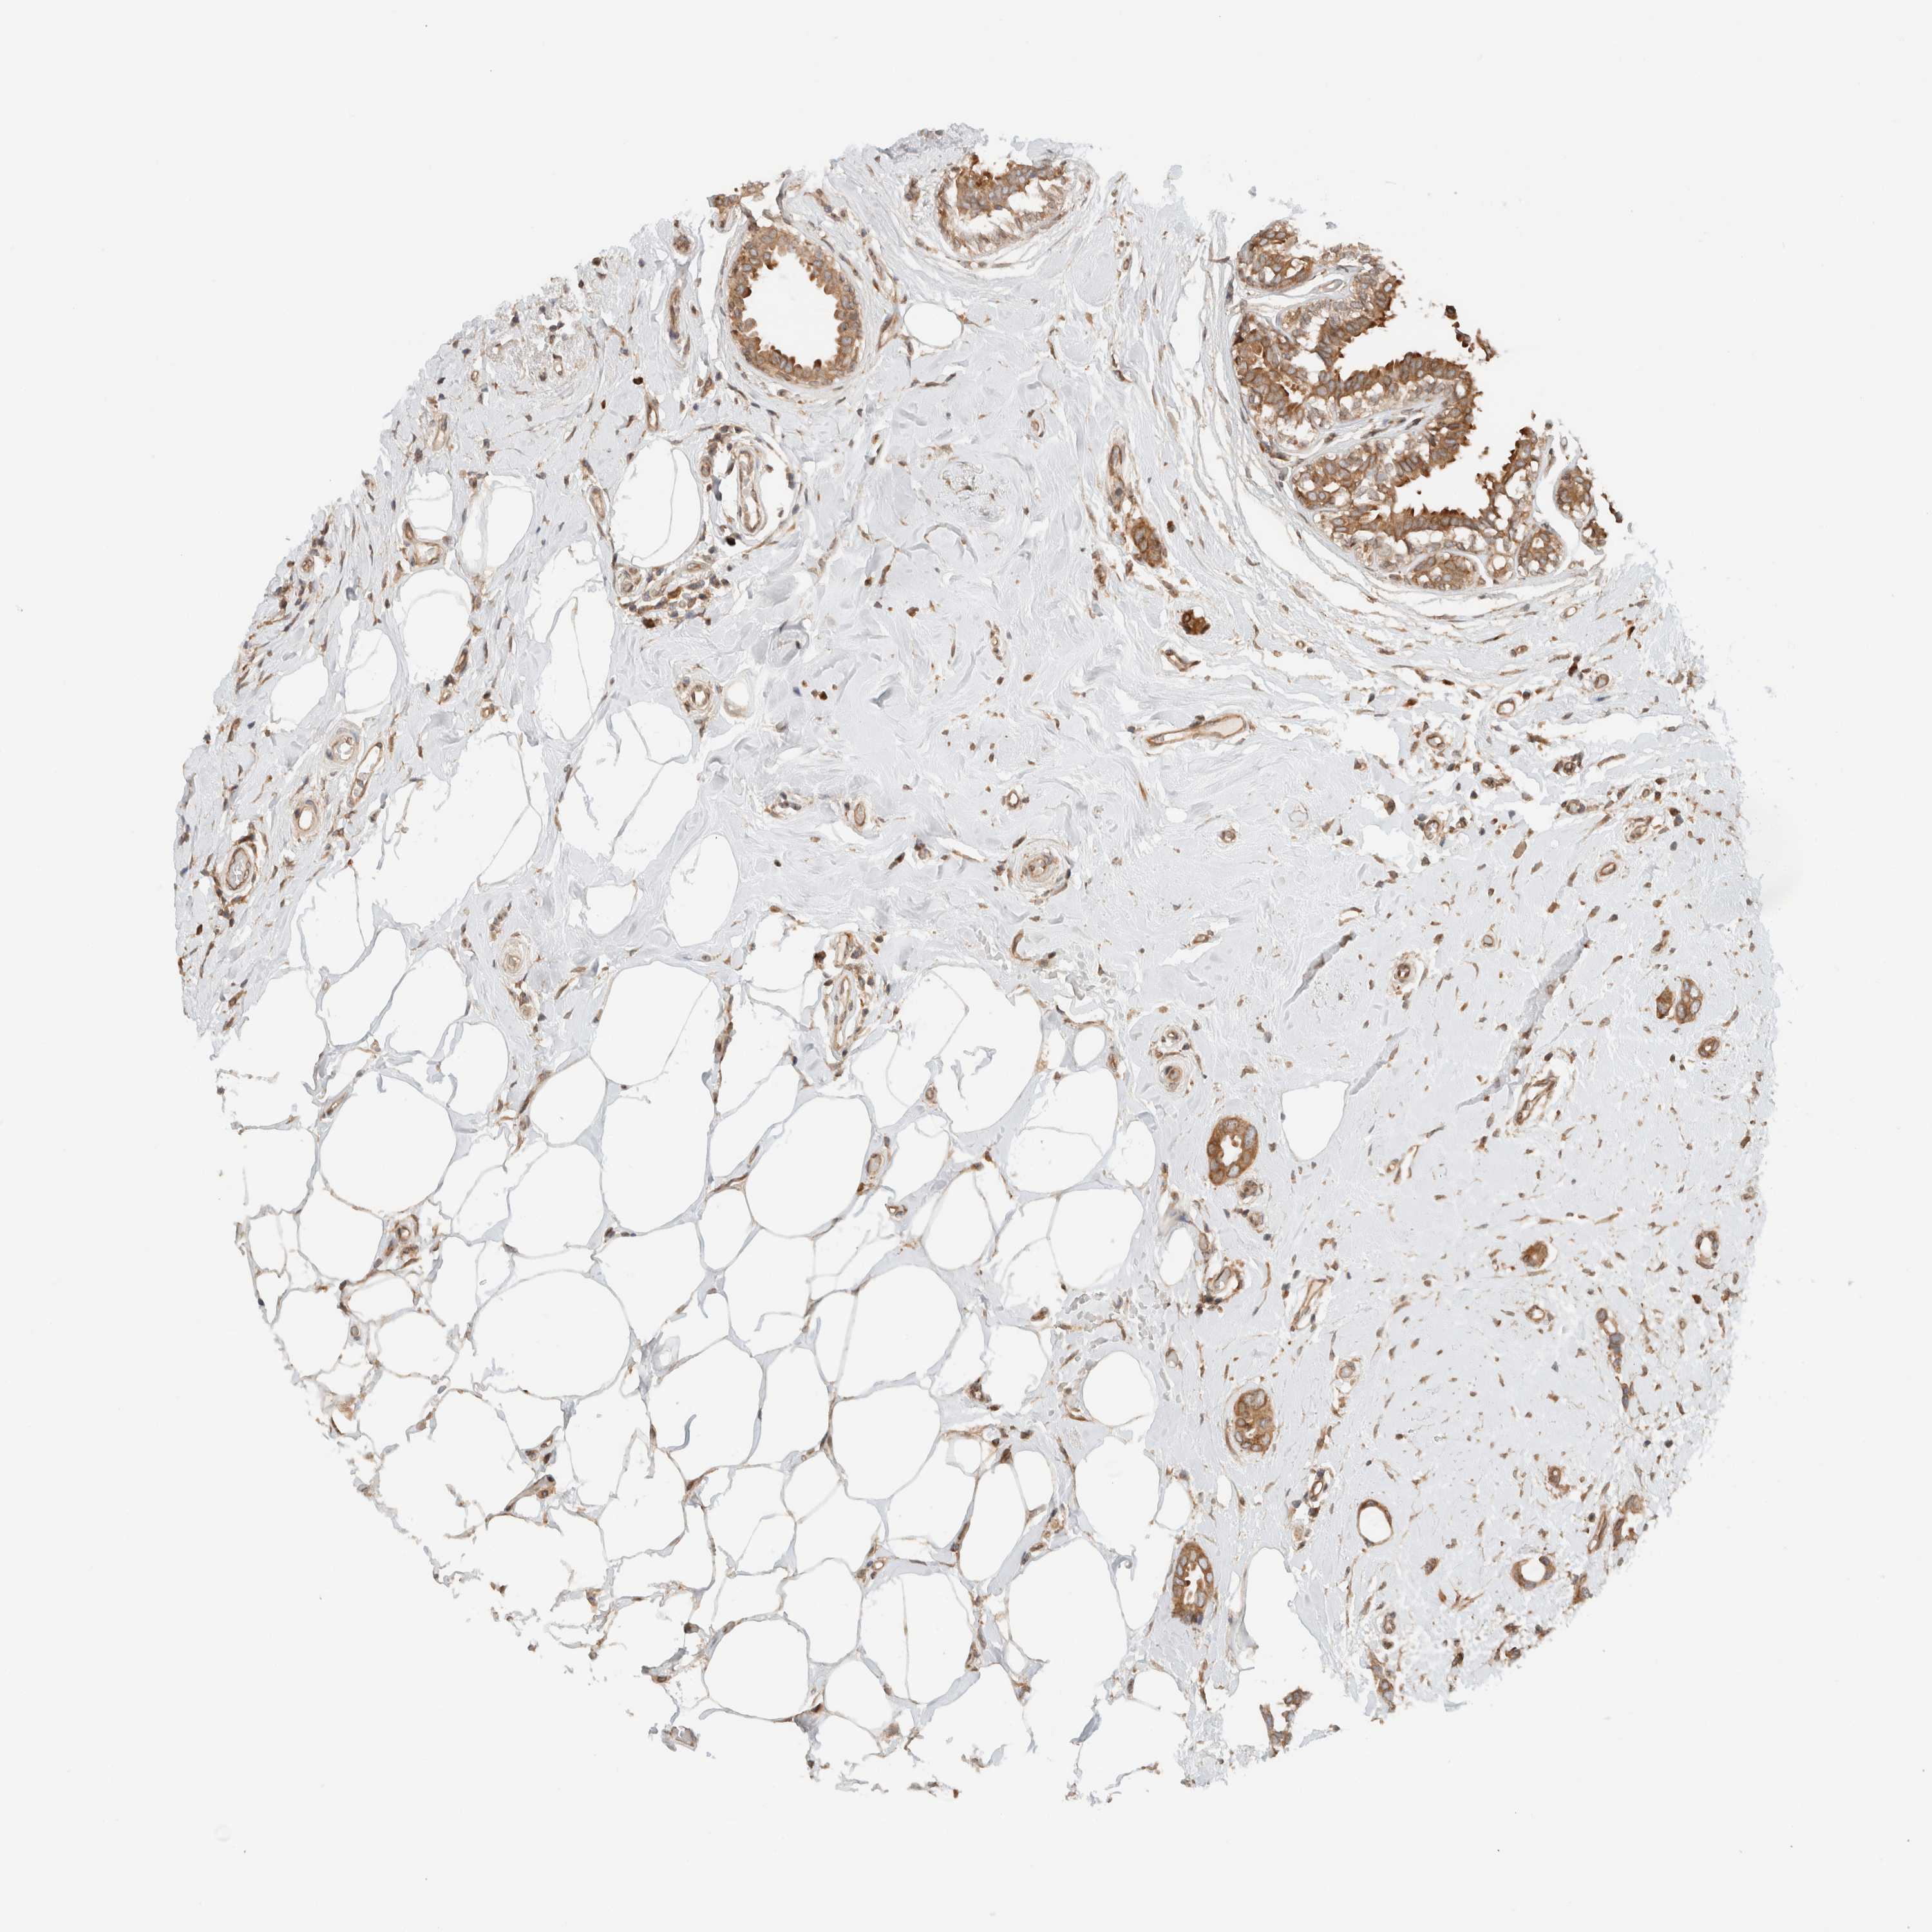

BRCA TCGA BRCA VALIDATION PROTEIN EXPRESSION